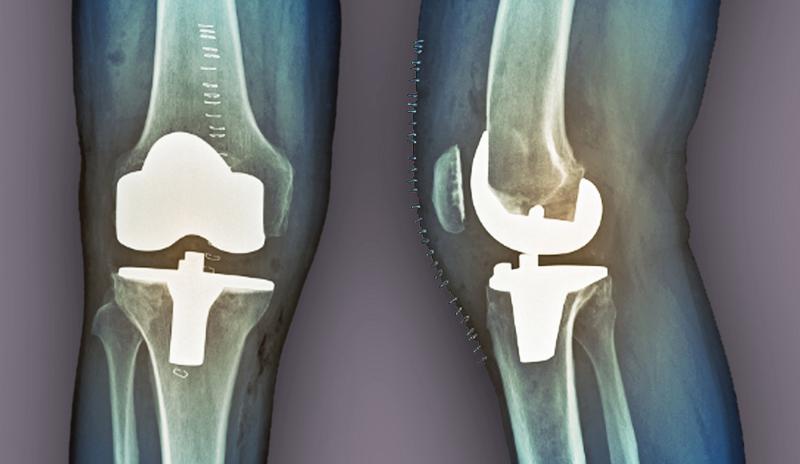

Diz kapağı kayması ameliyatından sonra ne kadar sürede ayağa kalkabiliriz? Ve şişlik ne kadar zamanda geçer? Ayrıca diz protezi cerrahisi gerektirebilecek durumları önlemek için nelere dikkat etmeliyiz?

Diz Protezi Cerrahisini Önlemek İçin Dikkat Edilmesi Gerekenler

Diz protezi cerrahisi gerektirebilecek durumları önlemek için aşağıdaki önlemleri almak faydalı olabilir: